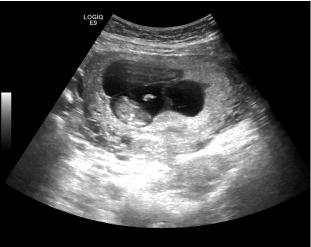

Further characterization of the lesion with pelvic magnetic resonance imaging (MRI) revealed a solid, sub-urothelial two centimetre bladder mass. This was in close relation to the cervix (Figure 2). Concerns between a benign or malignant process led to recommendation of direct visualisation (cystoscopy).

Figure 2 Magnetic resonance imaging of the abdomen and pelvis (coronal section): bladder lesion identified.